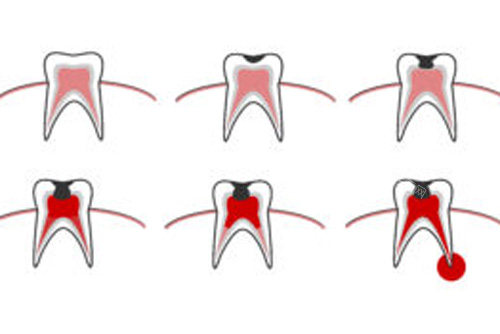

科室业务范围涵盖牙体牙髓病、牙周病、口腔黏膜病、口腔颌面外科、口腔预防、儿童口腔、口腔修复、口腔正畸、口腔种植科等。在意运用中西结合方法治疗口腔疾病,如牙周病、粘膜病等,颇具特色。